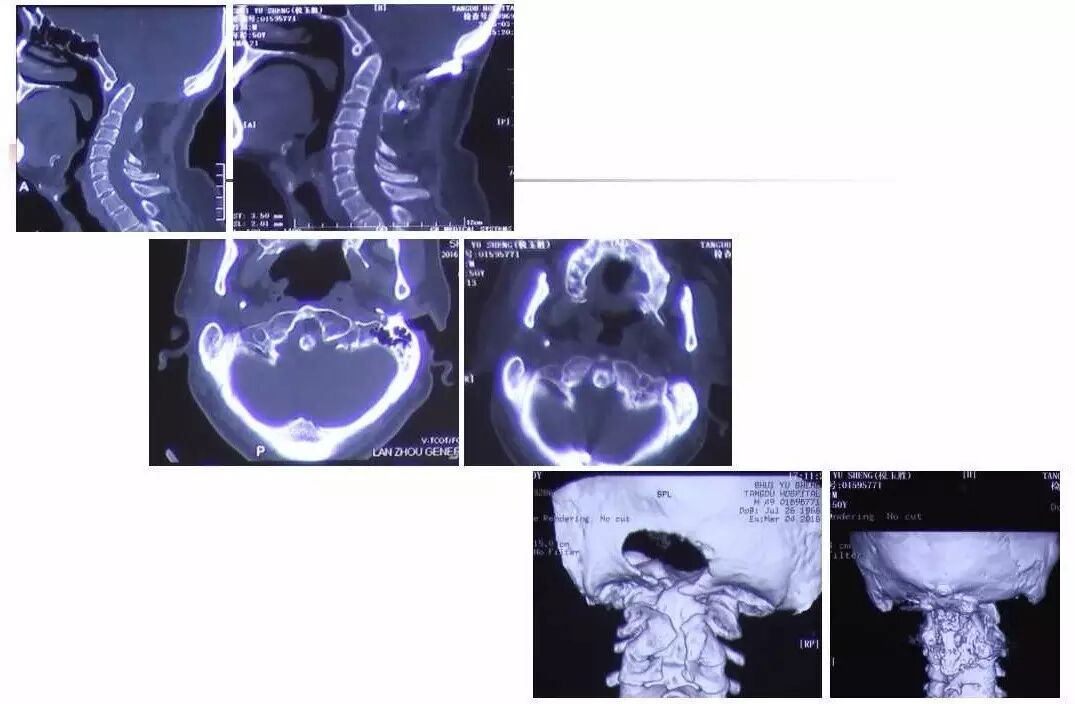

在脊柱神经外科、显微神经外科和颅底肿瘤外科前沿研究和临床诊治领域有着扎实的基础,为全国首批获得脊柱神经外科医师培训认证的神经外科医生。擅长颈椎病、椎管肿瘤及各种脊柱疑难疾病的诊治、脑肿瘤微创手术,尤其擅长颈椎退行性疾病的手术,率先在国内开展了颅底凹陷后路复位、颈前路减压融合等高难度手术,多年来收治了来自全国各地的大量患者,疗效达到国内领先水平。